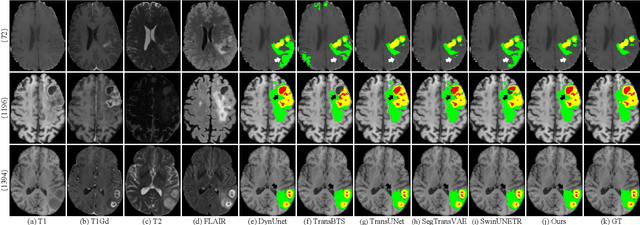

Abstract:Brain tumor segmentation (BTS) in magnetic resonance image (MRI) is crucial for brain tumor diagnosis, cancer management and research purposes. With the great success of the ten-year BraTS challenges as well as the advances of CNN and Transformer algorithms, a lot of outstanding BTS models have been proposed to tackle the difficulties of BTS in different technical aspects. However, existing studies hardly consider how to fuse the multi-modality images in a reasonable manner. In this paper, we leverage the clinical knowledge of how radiologists diagnose brain tumors from multiple MRI modalities and propose a clinical knowledge-driven brain tumor segmentation model, called CKD-TransBTS. Instead of directly concatenating all the modalities, we re-organize the input modalities by separating them into two groups according to the imaging principle of MRI. A dual-branch hybrid encoder with the proposed modality-correlated cross-attention block (MCCA) is designed to extract the multi-modality image features. The proposed model inherits the strengths from both Transformer and CNN with the local feature representation ability for precise lesion boundaries and long-range feature extraction for 3D volumetric images. To bridge the gap between Transformer and CNN features, we propose a Trans&CNN Feature Calibration block (TCFC) in the decoder. We compare the proposed model with five CNN-based models and six transformer-based models on the BraTS 2021 challenge dataset. Extensive experiments demonstrate that the proposed model achieves state-of-the-art brain tumor segmentation performance compared with all the competitors.